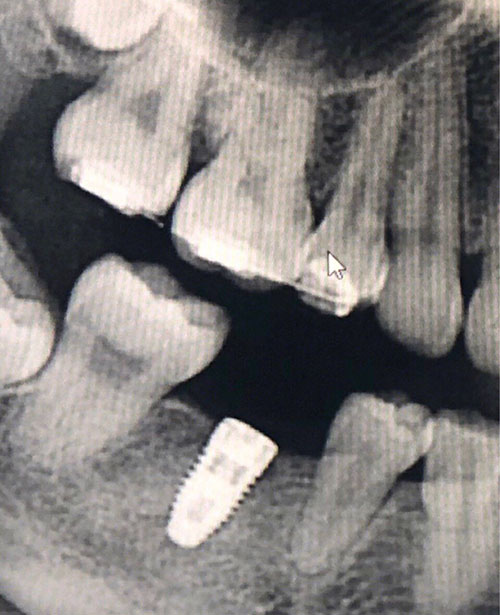

紹興國興口腔醫(yī)院種植牙69天,之前就想做種植牙,一直都沒有機會做,現(xiàn)在終于決定做了,拍片子,做治療,這家醫(yī)院很正規(guī)靠譜,張國興院長我也很信賴,后面我會持續(xù)更新~給你們看我種植后的術(shù)后照片的。

紹興國興口腔醫(yī)院種植牙